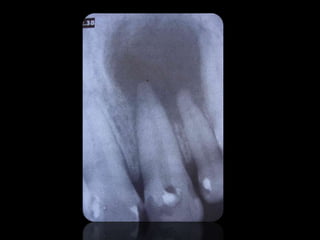

CARIES